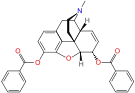

3,6-diesters of morphine

- Acetylpropionylmorphine

- 3,6-Dibutanoylmorphine

- Diacetyldihydromorphine (dihydroheroin, acetylmorphinol)

- Dibutyrylmorphine

- Dibenzoylmorphine (first designer drug)

- Diformylmorphine

- Dipropanoylmorphine

- Heroin (diacetylmorphine)

- Nicomorphine

Structures

| 3,6-diesters of morphine | ||||

|---|---|---|---|---|

Acetylpropionylmorphine Acetylpropionylmorphine |

3,6-Dibutanoylmorphine |  Diacetyldihydromorphine Diacetyldihydromorphine(dihydroheroin, acetylmorphinol) | ||

Dibutyrylmorphine Dibutyrylmorphine |

Dibenzoylmorphine Dibenzoylmorphine |

Diformylmorphine Diformylmorphine | ||

Dipropanoylmorphine Dipropanoylmorphine |

Heroin Heroin(diacetylmorphine) |

Nicomorphine Nicomorphine | ||